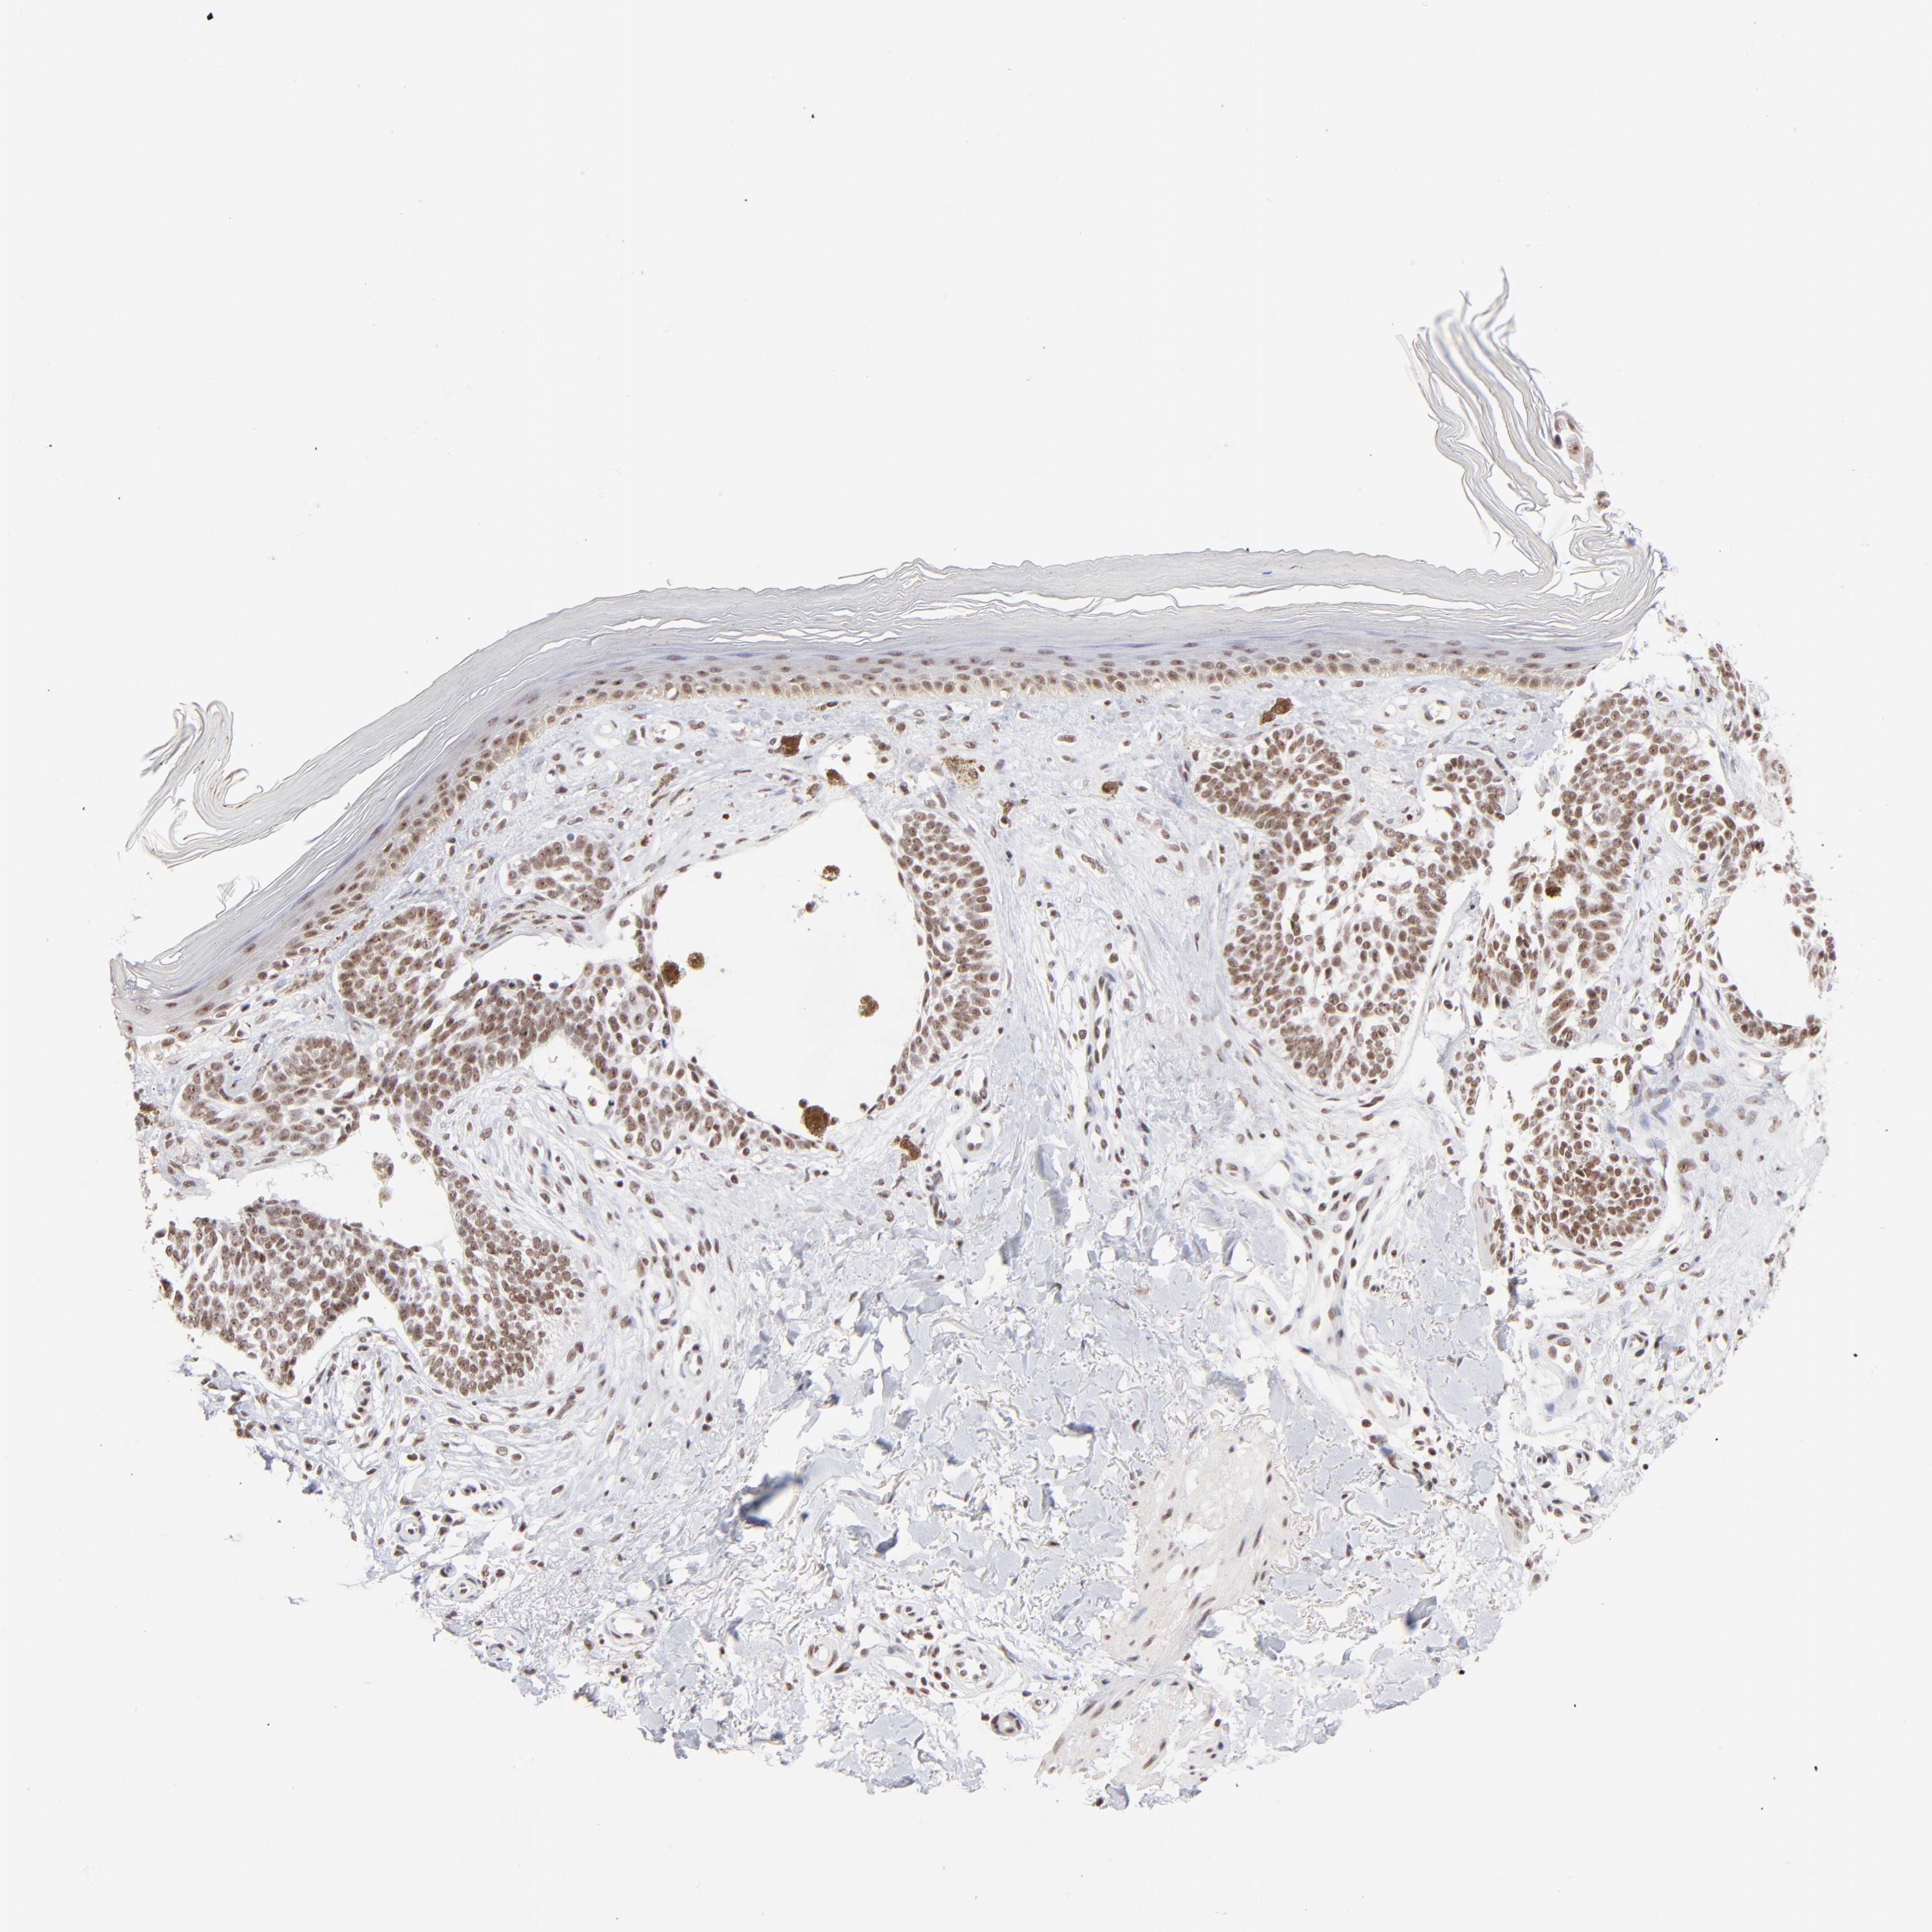

SKIN CANCER - Protein expressioni

A mouse-over function shows sample information and annotation data. Click on an image to view it in a full screen mode. Samples can be filtered based on level of antibody staining by selecting one or several of the following categories: high, medium, low and not detected. The assay and annotation is described here.

Antibody stainingi

Antibody staining in the annotated cell types in the current human tissue is reported as not detected, low, medium, or high, based on conventional immunohistochemistry profiling in selected tissues. This score is based on the combination of the staining intensity and fraction of stained cells.

Each image is clickable and will lead to virtual microscopy that enables deeper exploration of all samples and also displays staining intensity scores, fraction scores and subcellular localization as well as patient and tissue information for each sample.

Antibody HPA003263

Staining

High

Medium

Low

Not detected

Intensity

Strong

Moderate

Weak

Negative

Quantity

>75%

75%-25%

<25%

None

Location

Nuclear

Cytoplasmic/membranous

Cytoplasmic/membranous,nuclear

Squamous cell carcinoma, NOS

Basal cell carcinoma